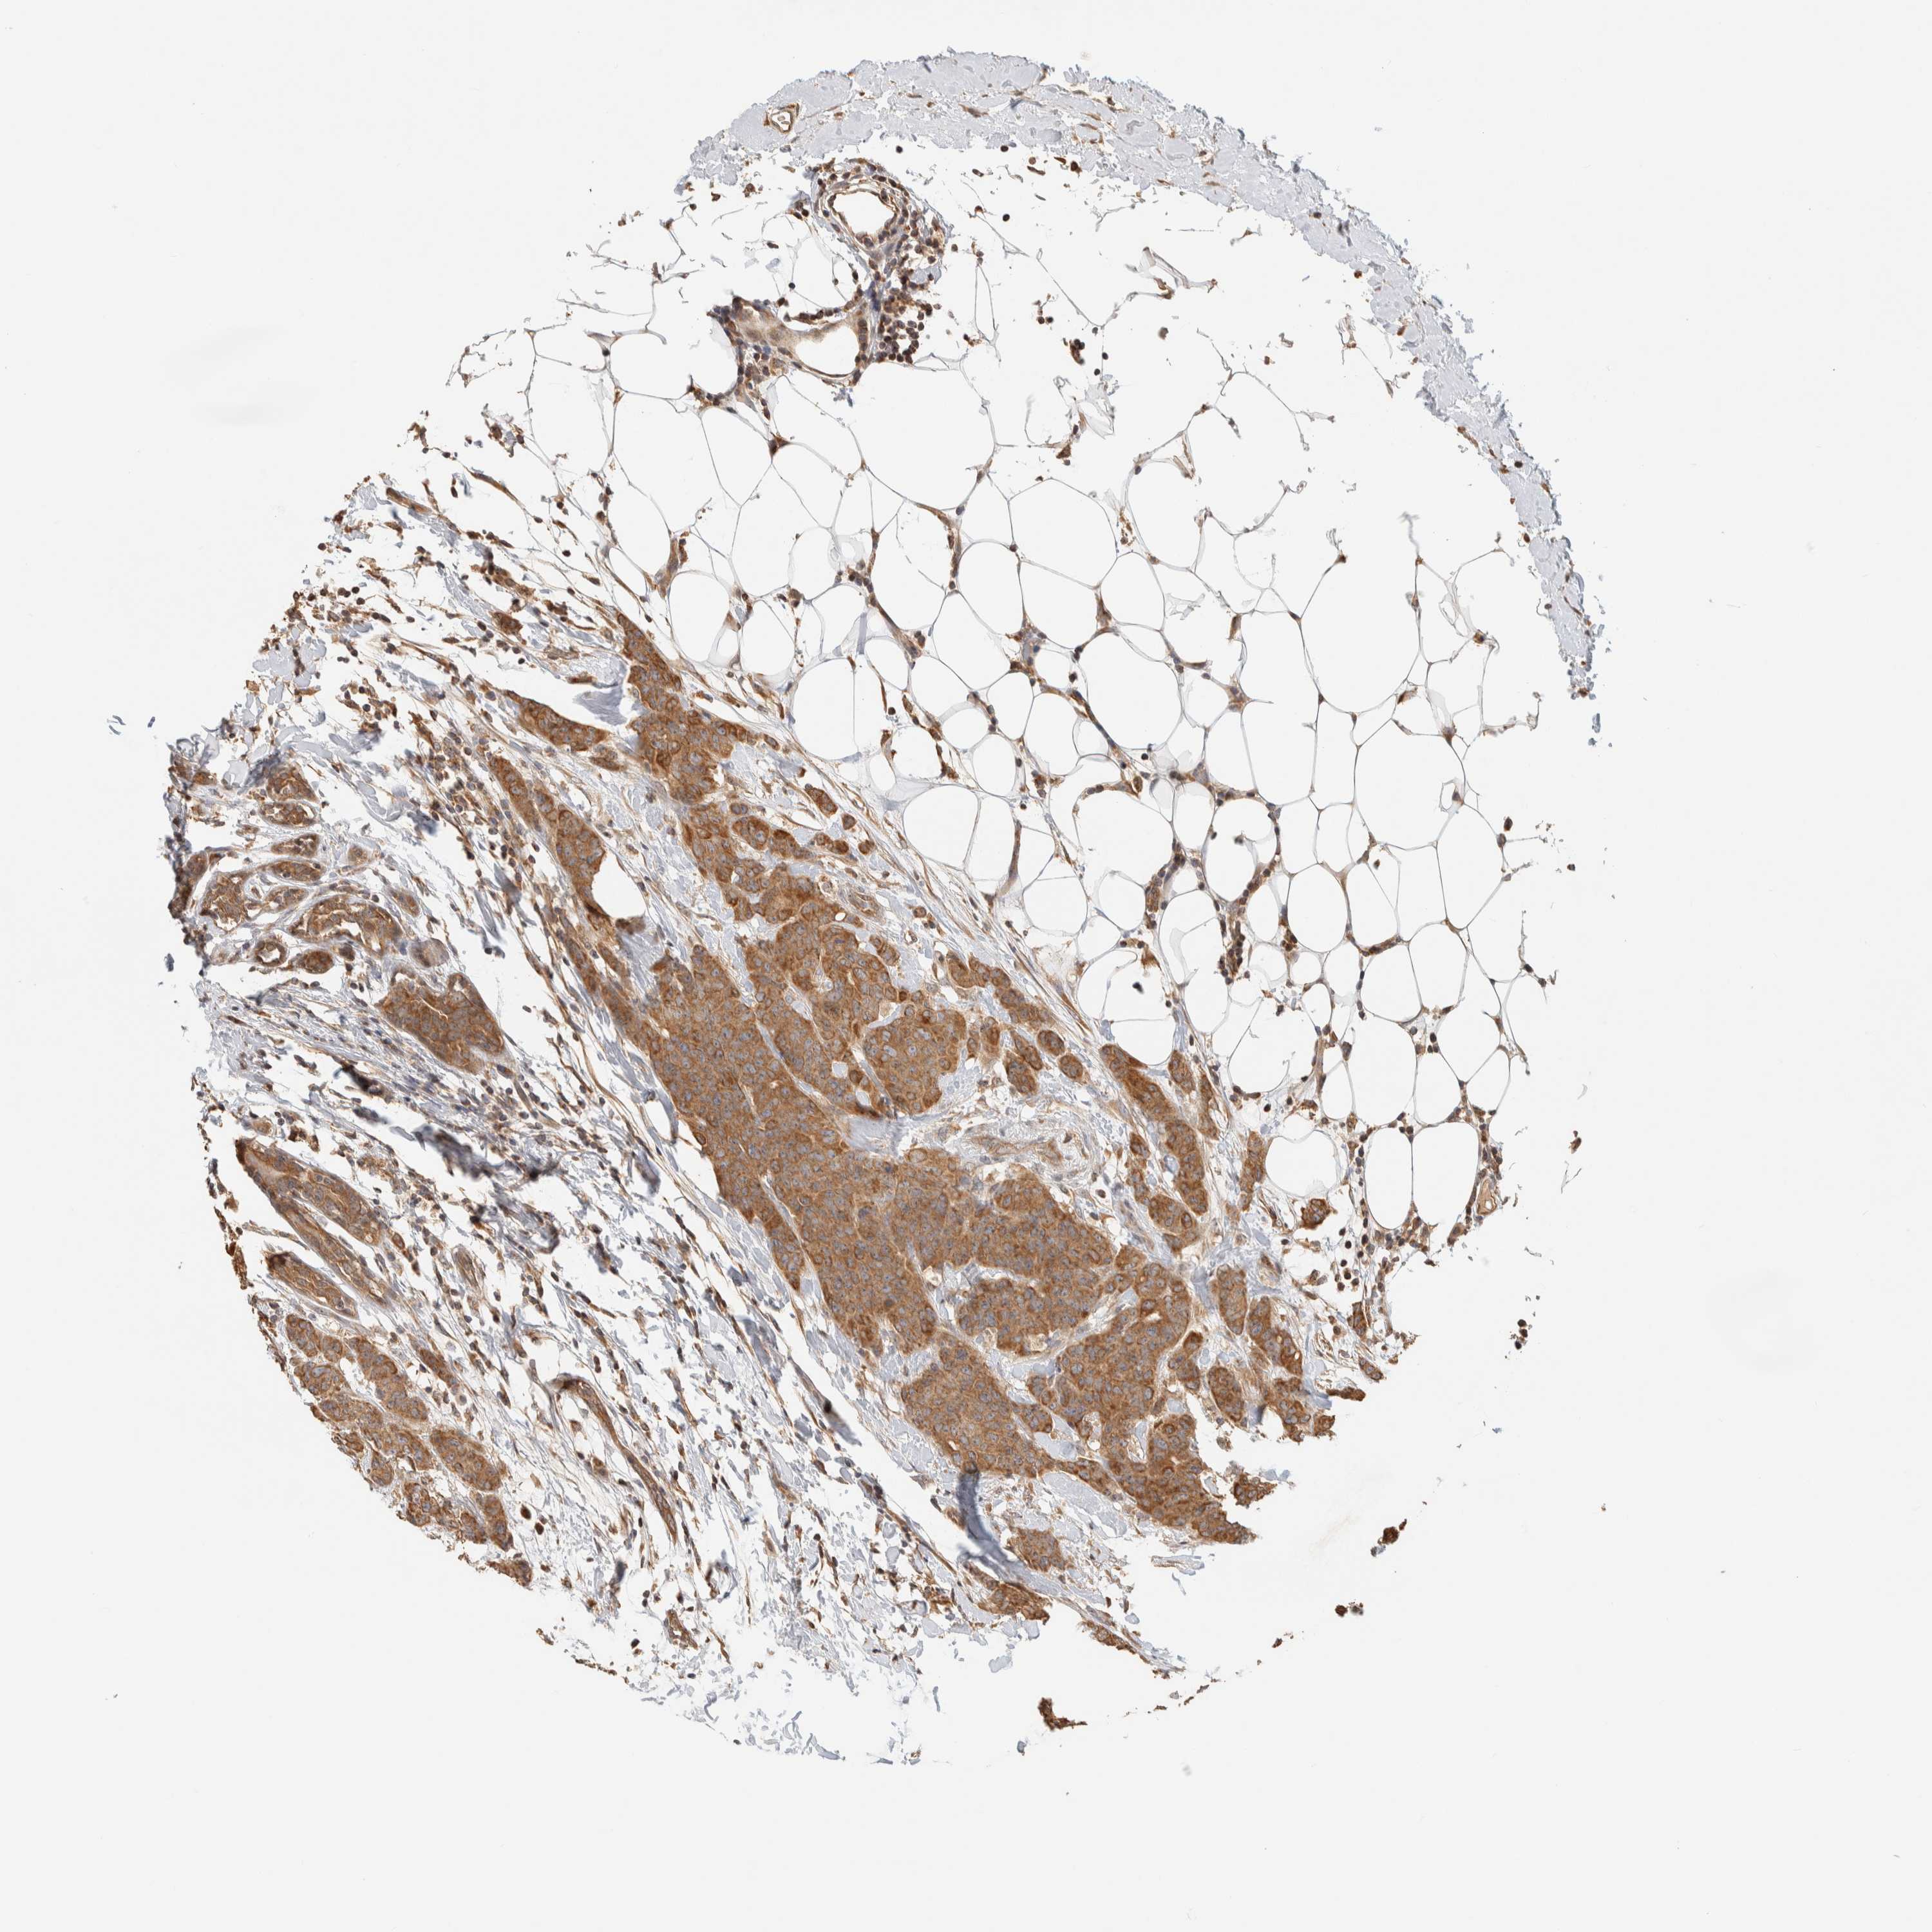

CANCER BREAST CANCER Show tissue menu

BRCA TCGA BRCA VALIDATION PROTEIN EXPRESSION

Breast cancer

Human cancer